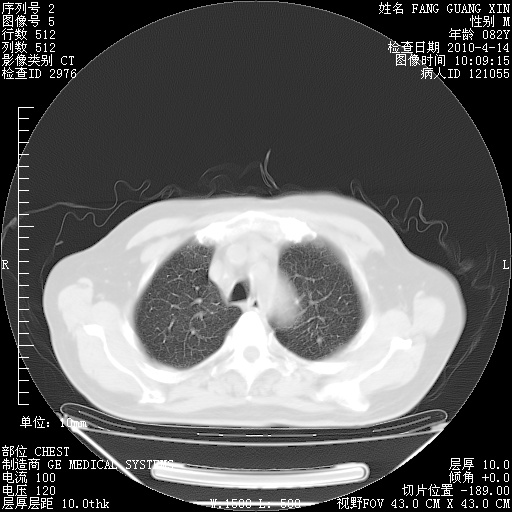

4月14日肺部CT